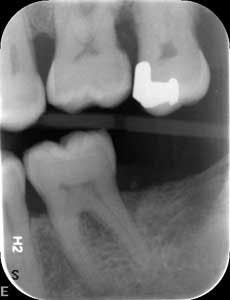

Dental examination revealed gingival swelling and bleeding on probing. Periodontal probing showed moderate-to-deep pocket depths in all posterior teeth (figures 1–3). Generalized bone loss was observed on radiographs (figures 4–6). Tooth vitality and percussion tests were negative. Teeth 2, 3, 31, 14, and 15 had Class III mobility. The patient was diagnosed with Type IV chronic adult periodontitis. Treatment options were discussed, and, after explanation, the patient agreed to the LANAP procedure.

Patient presentation before LANAP treatment (figures 1–6)